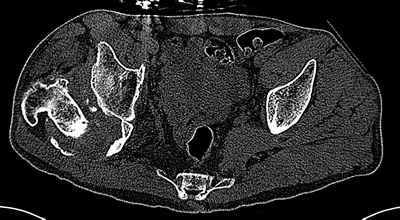

Уважаемые коллеги. Пациент 30 лет 3 года назад в результате травмы получил травматический дефект нижних конечностей до в/3 голеней, был пропущен вывих бедра.

В настоящее время очень неплохо ходит на протезах, движения в неоартрозе близки по объему к здоровой стороне. Основная жалоба - выраженная боль при ходьбе. планируем двухэтапное эндопротезирование - задним доступом мобилизовать проксимальный отдел бедра, резецировать шейку, аппаратом низвести бедро(головку оставить там где она есть, так как больших дефектов не видно(может пригодится в последующем?)). Вторым этапом бесцементное эндопротезирование. Насколько такой вариант реалистичен? Доступ для второго этапа? Может быть другие варианты?С уважением, Максим

На последнем срезе КТ задний край практически отсутсвует по сравнения со здоровой стороной. Разумеется, что это плоскостное изображение, но головка вывихнулась не только в плоскостную щель захваченную на КТ. Если вы считаете, что удастся установить туда чашку даже низкопрофильную, остается пожелать вам успехов. Но перед этим можно смоделировать установку чашки на скиаграммах КТ.

За пожелание успехов - спасибо, думаю это пригодится, не очень понял про плоскостную щель, специально предоставил срезы на уровне свода - он цел, дефект заднего края ниже, за счет заглубления он будет еще меньше, по данным 3d - должно получиться.